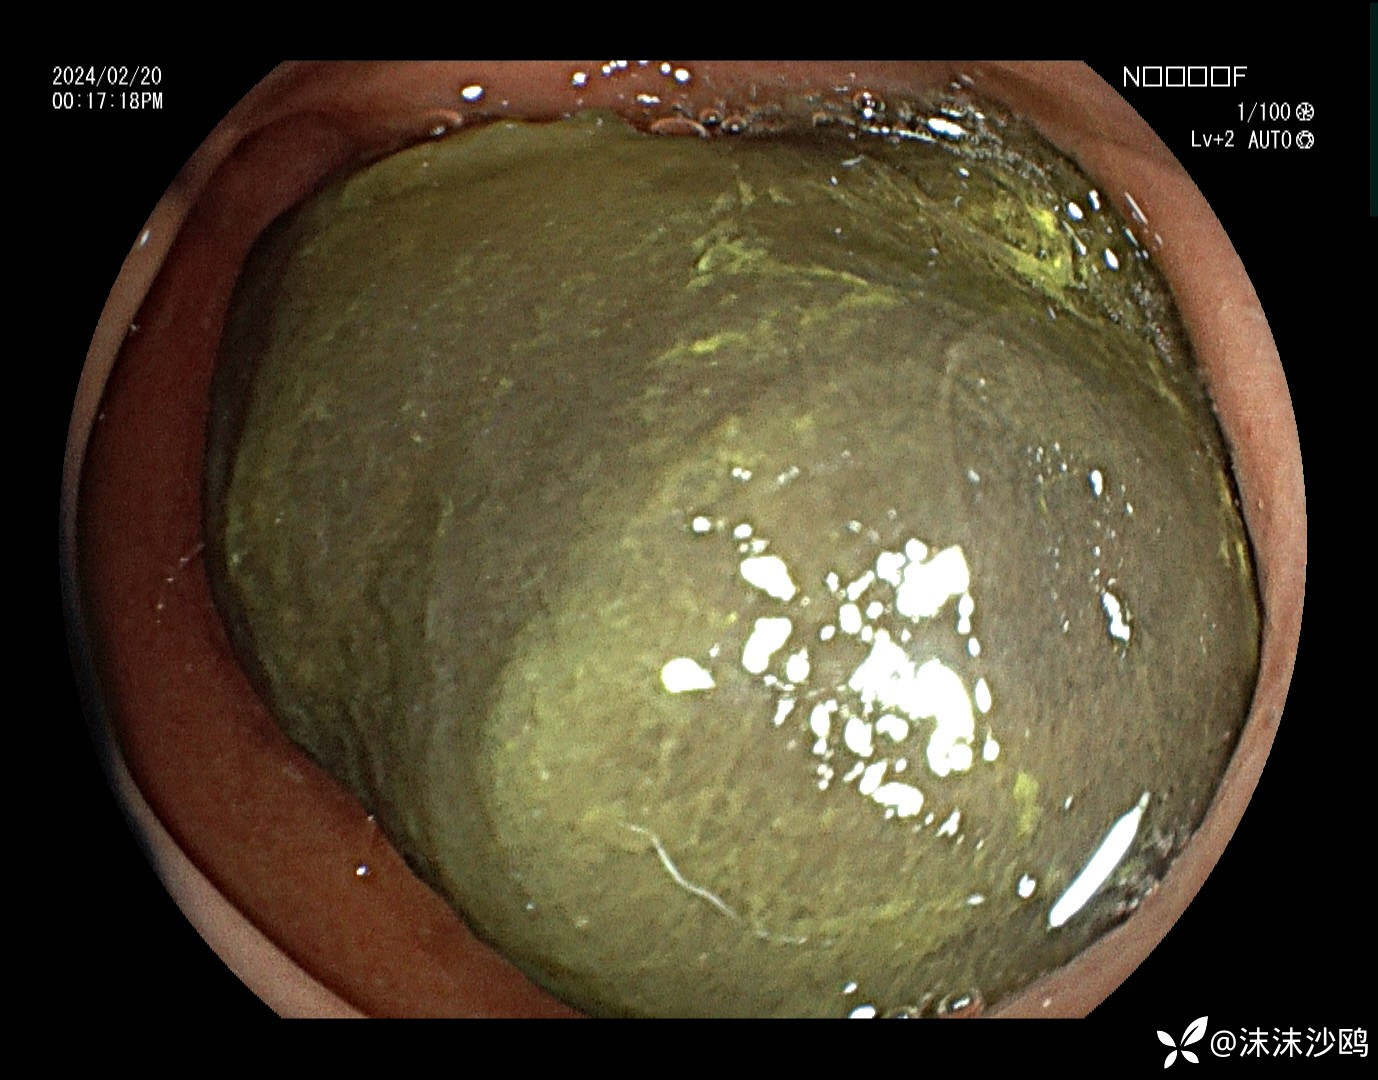

中年男子,腹痛就诊,行普通肠镜检查。胃腔内见大量胃液潴留,吸引了三四百毫升。进到幽门有了发现。

巨大异物嵌顿在球部,考虑胃石导致梗阻。询问病史,就是吃了几个车厘子,没有吃柿子或者山楂之类的。